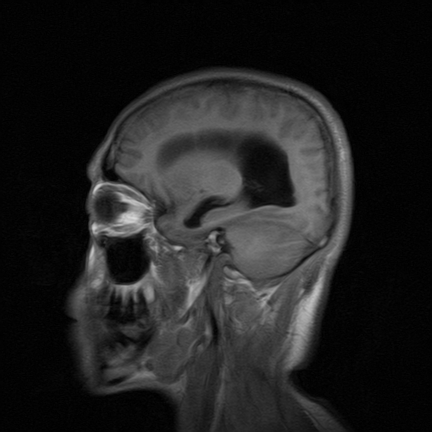

标题: MRI2064:少见病例。男性52,视力下降多年。 [打印本页]

标题: MRI2064:少见病例。男性52,视力下降多年。

四脑室区见混杂信号占位影,脑室系统扩张明显,临近结构显著受压称位,患者52岁,多考虑室管膜瘤可能性大

定位;脑室内富血供占位

应该是来源于小脑蚓部的占位,如血管母细瘤或星形细胞瘤

小脑蚓部胶质脑膜瘤突入四脑室;肿瘤内见血管流空信号和钙化信号.

比较典型的脉络丛乳头状瘤并脑积水,鉴别小脑蚓部血管母细胞瘤。